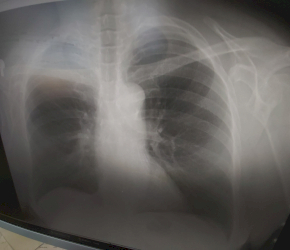

Rekonstrukcí projde celé pracoviště včetně vybavení. Budeme mít zcela nový RTG přístroj.

Už teď je vše digitalizováno a lékař ihned obdrží RTG snímek po rentgenu pacienta. Pracoviště neslouží jen Ambulantnímu centru Nemocnice Žižkov, ale i jako RTG pro další lékaře.